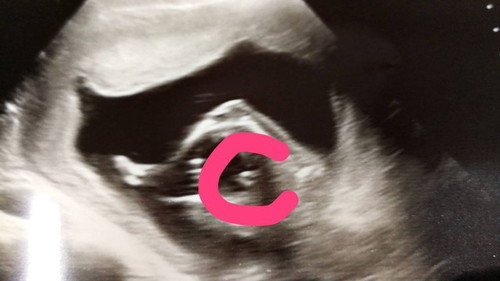

อัลตร้าซาวด์เพศหญิงหรือชายคะแม่ๆช่วยดูหน่อยคะ

เหมือนจะหญิงค่ะ😊